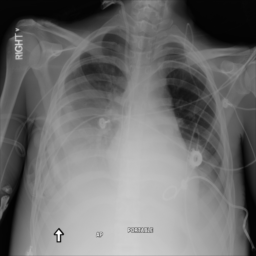

Anomaly detection is the problem of recognizing abnormal inputs based on the seen examples of normal data. Despite recent advances of deep learning in recognizing image anomalies, these methods still prove incapable of handling complex medical images, such as barely visible abnormalities in chest X-rays and metastases in lymph nodes. To address this problem, we introduce a new powerful method of image anomaly detection. It relies on the classical autoencoder approach with a re-designed training pipeline to handle high-resolution, complex images and a robust way of computing an image abnormality score. We revisit the very problem statement of fully unsupervised anomaly detection, where no abnormal examples at all are provided during the model setup. We propose to relax this unrealistic assumption by using a very small number of anomalies of confined variability merely to initiate the search of hyperparameters of the model. We evaluate our solution on natural image datasets with a known benchmark, as well as on two medical datasets containing radiology and digital pathology images. The proposed approach suggests a new strong baseline for image anomaly detection and outperforms state-of-the-art approaches in complex medical image analysis tasks.